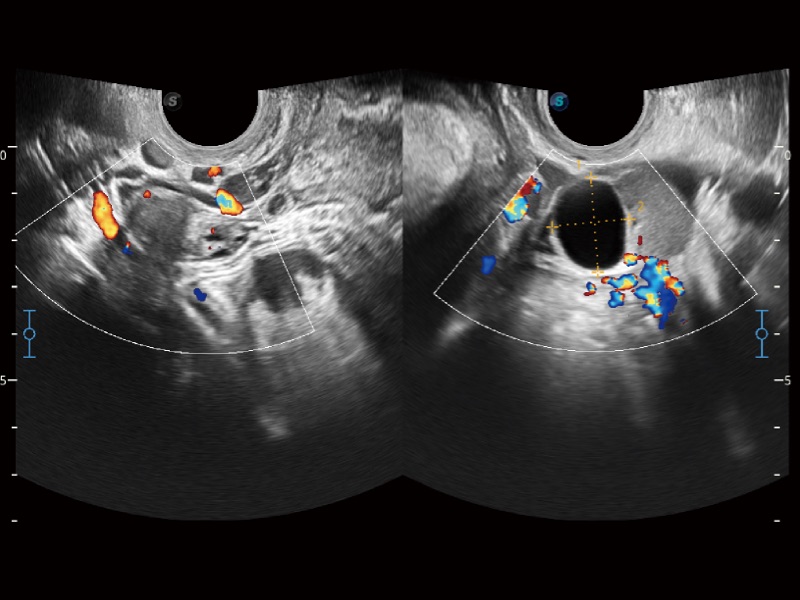

• 妇产科应用

临床图